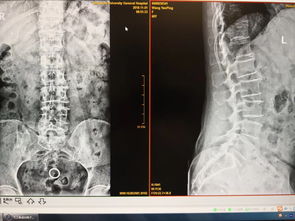

腰痛-腰痛腿麻当椎间盘突出,脊柱外科医生看了片子说椎管里长了

腰痛伴随腿麻,是骨科与脊柱外科门诊中最常见的症状组合之一。对于许多患者乃至部分非专科医生而言,这一症状组合的首选诊断往往是“腰椎间盘突出症”。确实,椎间盘退变、纤维环破裂导致髓核突出,压迫神经根或脊髓,是引起此类症状的最常见病理基础。典型的症状包括腰部疼痛,以及向下肢放射的疼痛、麻木或无力感,在咳嗽、打喷嚏或久坐时可能加重。影像学检查,尤其是磁共振成像(MR...